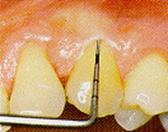

Sonda y procedimientos de sondaje:

Se usa la sonda periodontal

diseñada por la OMS para el CPITN (Morita, Japón), o sondas periodontales

tipo OMS (Hu-Friedy).

Esta sonda está particularmente

diseñada para una manipulación suave de los tejidos blandos ubicados

alrededor de la pieza dentaria. La sonda presenta una esfera de 0,5 mm. de

diámetro en el extremo, con una porción codificada de color que se extiende

desde los 3,5 a los 5,5 mm.

Debe usarse una fuerza suave para

determinar la profundidad de la bolsa y para detectar la presencia de

cálculo subgingival. Esta presión no debe ser mayor de 20 gramos. La sonda

se introduce entre el diente y la encía, lo más paralelamente posible a la

superficie de la raíz. La profundidad del surco gingivodentario se determina

observando el código de color o marca, al nivel del margen gingival. El

extremo de la sonda debe mantener el contacto con la superficie de la raíz.